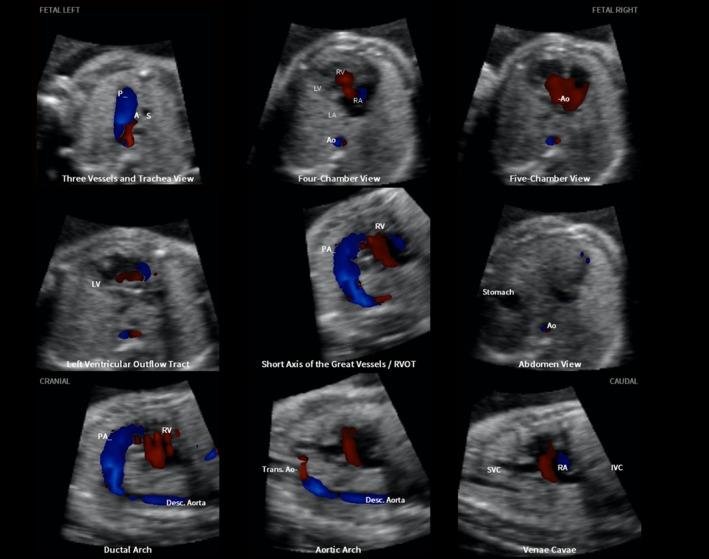

A prospective cohort study was conducted of fetuses in the second and third trimesters with a normal heart or with congenital heart disease (CHD). One or more spatiotemporal image correlation (STIC) volume datasets, combined with color or bidirectional power Doppler (S-flow) imaging, were acquired in the apical four-chamber view. Each successfully obtained STIC volume was evaluated by STICLoop™ to determine its appropriateness before applying the FINE method. Visualization rates for standard fetal echocardiography views using diagnostic planes and/or Virtual Intelligent Sonographer Assistance (VIS-Assistance®) were calculated for grayscale (removal of Doppler signal), color Doppler and S-flow Doppler. In four cases with CHD (one case each of tetralogy of Fallot, hypoplastic left heart and coarctation of the aorta, interrupted inferior vena cava with azygos vein continuation and asplenia, and coarctation of the aorta with tricuspid regurgitation and hydrops), the diagnostic potential of this new technology was presented.

A total of 169 STIC volume datasets of the normal fetal heart (color Doppler, n = 78; S-flow Doppler, n = 91) were obtained from 37 patients. Only a single STIC volume of color Doppler and/or a single volume of S-flow Doppler per patient were analyzed using FINE. Therefore, 60 STIC volumes (color Doppler, n = 27; S-flow Doppler, n = 33) comprised the final study group. Median gestational age at sonographic examination was 23 (interquartile range, 21-27.5) weeks. Color Doppler FINE generated nine fetal echocardiography views (grayscale) using (1) diagnostic planes in 73-100% of cases, (2) VIS-Assistance in 100% of cases, and (3) a combination of diagnostic planes and/or VIS-Assistance in 100% of cases. The rate of generating successfully eight fetal echocardiography views with appropriate color and S-flow Doppler information was 89-100% and 91-100% of cases, respectively, using a combination of diagnostic planes and/or VIS-Assistance. However, the success rate for the ninth echocardiography view (i.e. superior and inferior venae cavae) was 33% and 30% for color and S-flow Doppler, respectively. In all four cases of CHD, color Doppler FINE demonstrated evidence of abnormal fetal cardiac anatomy and/or hemodynamic flow.

CONCLUSIONS

The FINE method applied to STIC volumes of normal fetal hearts acquired with color or bidirectional power Doppler information can generate successfully eight to nine standard fetal echocardiography views (via grayscale, color Doppler or power Doppler) in the second and third trimesters. In cases of CHD, color Doppler FINE demonstrates successfully abnormal anatomy and/or Doppler flow characteristics. Published 2017. This article is a U.S. Government work and is in the public domain in the USA. Ultrasound in Obstetrics & Gynecology published by John Wiley & Sons Ltd on behalf of the International Society of Ultrasound in Obstetrics and Gynecology.